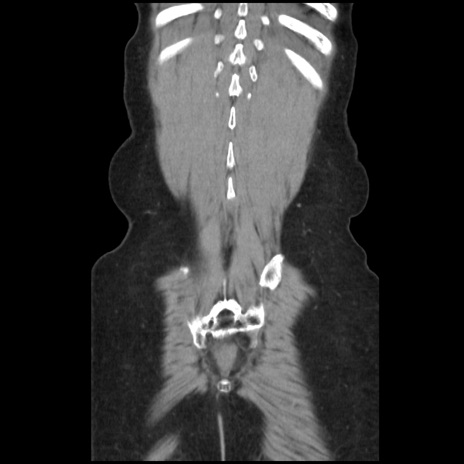

横断像